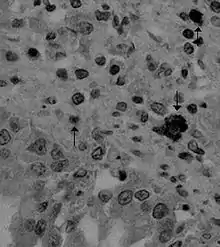

| 單株抗體偵測到狗的肺組織中具有犬冠状病毒 | |